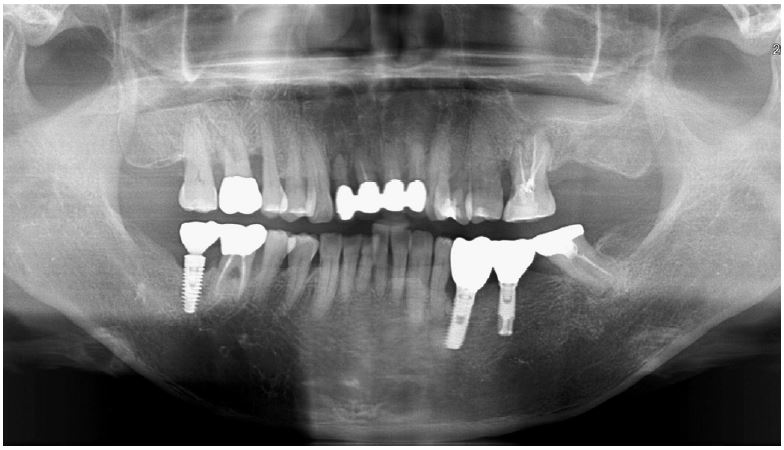

Clinical examination revealed bleeding on probing with a 7 mm PD of the buccal furcation of the maxillary right first molar (#16). Radiographic examination confirmed apically involved alveolar bone loss in the buccal roots of the mandibular first molars. (Fig. 7). It was assumed that initial stability could be achieved in the apical and septal bones, and extraction and iARP were planned. The patient was instructed to rinse with 0.12% chlorhexidine digluconate solution for 2 minutes for oral disinfection. The tooth was extracted using luxators and extraction forceps under local anesthesia with 2% lidocaine containing 1:80,000 epinephrine (Fig. 8A, 8B). After debridement of granulation tissues and irrigation with a sterile normal saline solution, immediate implant placement at the septal bone (TS III 5.0 × 8.5 mm; OSSTEM) was performed (Fig. 8C). The ISQ value at 1st surgery was 60. The gap between the implant surface and the extraction socket wall was filled with DBBM and covered with NBCM in a double-layer fashion (Fig. 8D). Thereafter, the hidden X suture and horizontal mattress suture were placed over NBCM without primary wound closure (Fig. 8E, 8F). Fourteen days after surgery, the patient returned for suture removal and postoperative examination. A delayed healing pattern with yellowish granulation tissue above the extraction socket was observed, and a depressed healing pattern of soft tissue with exposure to the cover screw was observed even after four weeks (Fig. 8G, 8H).

Fig. 8.

Case 2: Clinical photographs of the immediate implant placement with alveolar ridge preservation. (A) Initial clinical photograph of the maxillary right first molar, (B) Buccal gingival tears observed after tooth extraction, (C) Immediate implant placement in the septal bone, (D) Deproteinized bovine bone mineral was placed in the extraction socket, (E) Hidden X and horizontal mattress sutures are placed over the native bilayer collagen membrane, (F) Panoramic radiograph after implant placement, (G) Delayed gingival healing with yellowish granulation tissue observed at stitch out (2 weeks), (H) Cover screw exposure with depressed gingival healing was observed during a recall check (4 weeks).